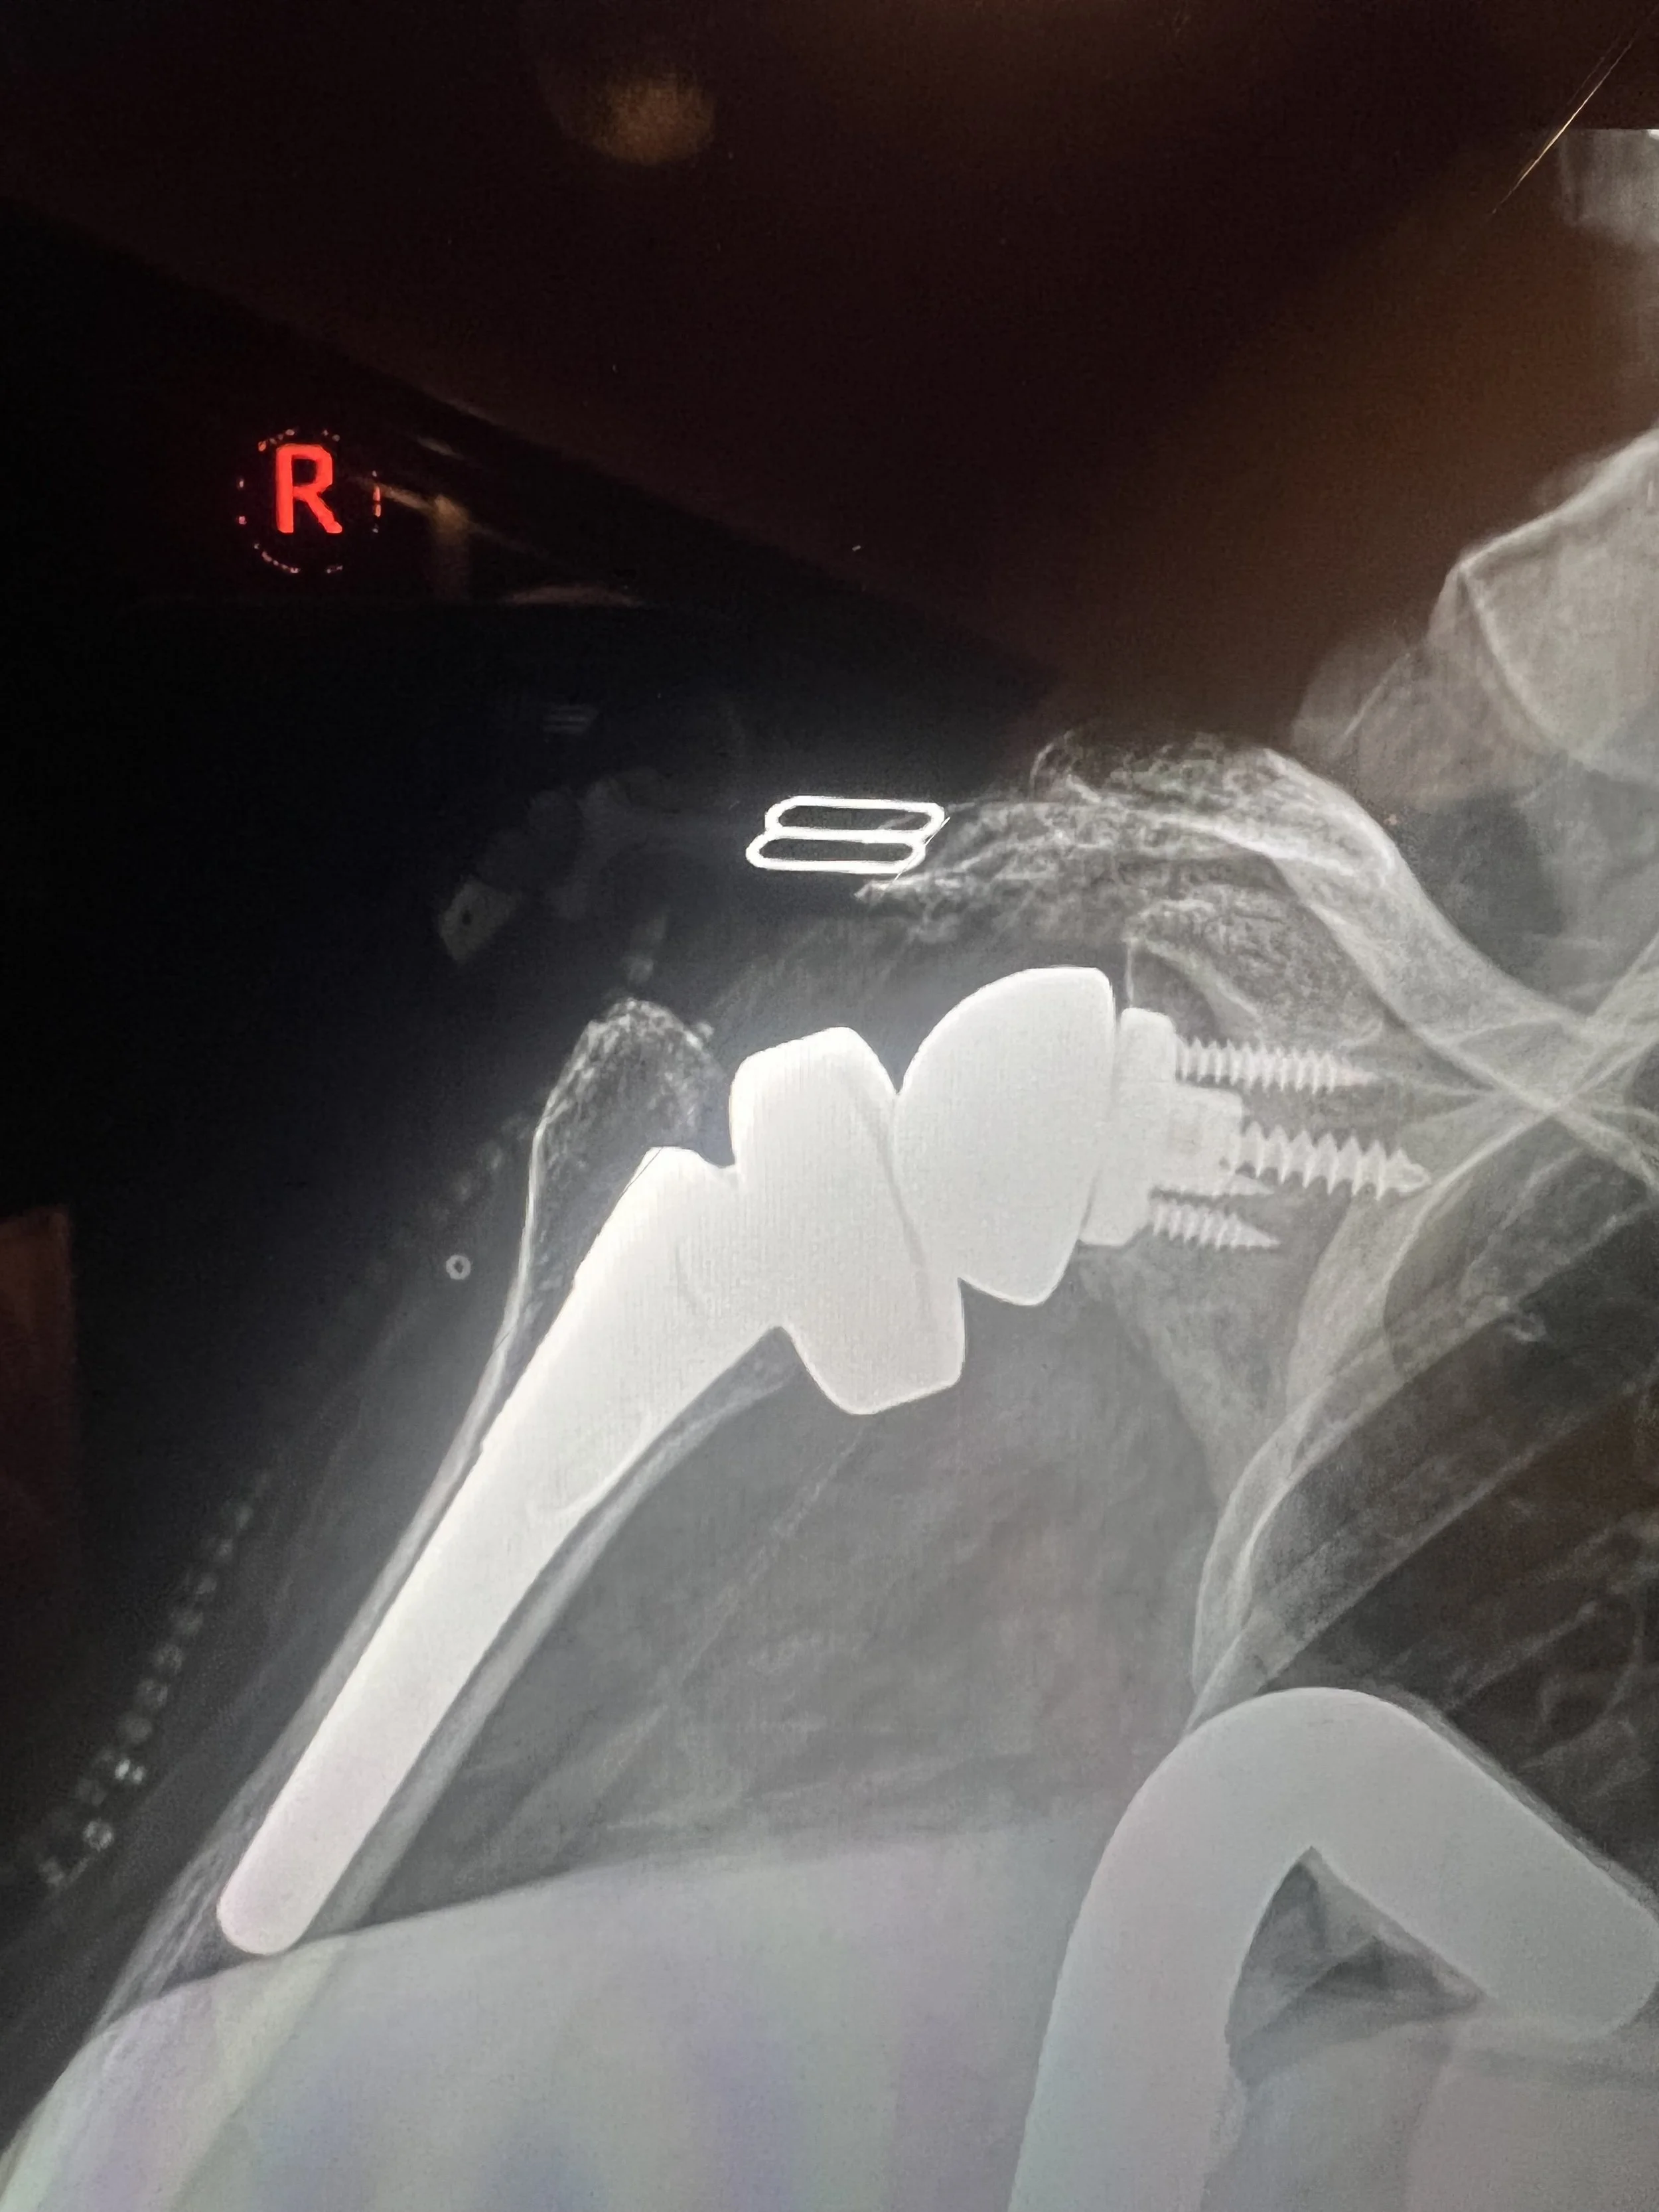

Reverse Total Shoulder Replacement

We specialize in reverse total shoulder replacement, a cutting-edge procedure designed for individuals who suffer from severe shoulder arthritis with coexisting rotator cuff tears. This innovative surgical approach not only alleviates pain but also restores function and mobility to those who previously had limited options for relief.